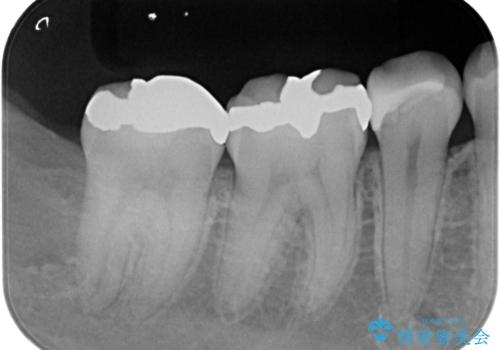

レントゲンで見つかった歯と歯の間の虫歯をセラミックインレーで修復

- 定期検診でレントゲンを撮ったら虫歯(カリエス)があったため、e-maxインレーにて治療しました。